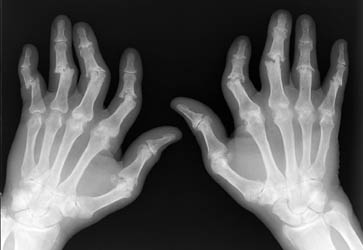

Psoriatic arthritis is an asymmetric process primarily with distal involvement of the hands. There are five different patterns of psoriatic arthropathy which are described in the following section. It is important to note that patients will usually exhibit findings which include more that one of these subsets.

Erosions will usually begin at the peripheral articular surfaces and extend centrally. Fluffy bone periostitis and erosions at the interphalangeal joints can create an appearance which resembles "mouse ears".

As previously mentioned, there are five different patterns of psoriatic arthritis. Classic psoriatic arthritis or DIP arthritis, involves the distal digits with associated fingernail pathology. Resorption of the distal phlangeal tufts can often be seen; this is a process called acroosteolysis. Arthritis mutilans, is a very destructive form of psoriatic arthritis with significant periarticular bone resorption. The erosions can cause a "pencil in cup" deformity where one articular surface is eroded creating a pointed appearance; the articulating bone can be concave, resembling an upside down cup. Symmetric polyarthropathy, can strongly resemble rheumatoid arthritis with erosions and ankylosis of the interphalangeal joints. Asymmetrical oligoarthritis, has the appearance of soft tissue swelling of a single phalanx known as a "sausage digit". The fifth and last pattern exhibits findings similar to ankylosing spondylitis with spinal sendesmophytes which occur in an asymmetric distribution. This is associated with sacroilitis which will usually present in an asymmetric and unilateral pattern.

Radiographic findings of the hand in an asymmetrical distribution distally without periarticular osteoporosis can help to differentiate psoriatic arthritis from rheumatoid arthritis. Overlapping patterns of the two disease processes can often make it difficult to distinguish one from the other. Furthermore, a patient can concurrently have psoriatic and rheumatoid arthritis. Reiter's syndrome can be distinguished from psoriatic arthritis by its tendency to involve only the articulations of the lower extremities.